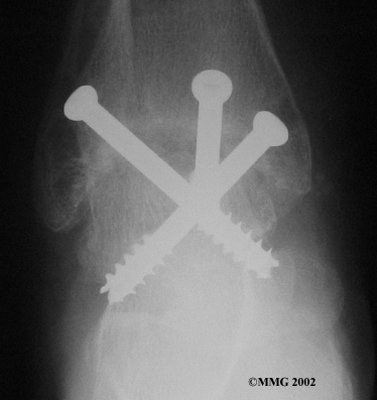

It is important when the surfaces are removed that the angles of the cut surfaces are correct. When the tibia is brought against the talus, the foot should be at a right angle to the lower leg. Once the cuts are made the bones must be held in place while they fuse. This can be done using large metal screws and metal plates if necessary. The screws are usually under the skin and are not removed unless they begin to rub and cause pain.

Inserting the screws

After ankle fusion, the physical therapists at FYZICAL Sun City Las Vegas can help you learn to walk smoothly and without a limp. Although time needed for recovery varies among patients, an ankle brace will typically replace your cast after eight to 12 weeks. Your surgeon will take X-rays frequently to see if the bones are fusing together. You will probably need to use crutches during the time you wear the cast. As the fusion grows stronger, you will begin to put more weight on your foot when walking.